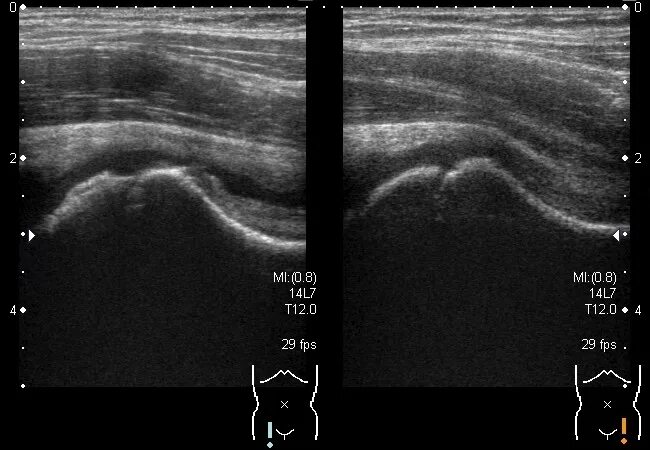

Где сделать узи тазобедренного сустава